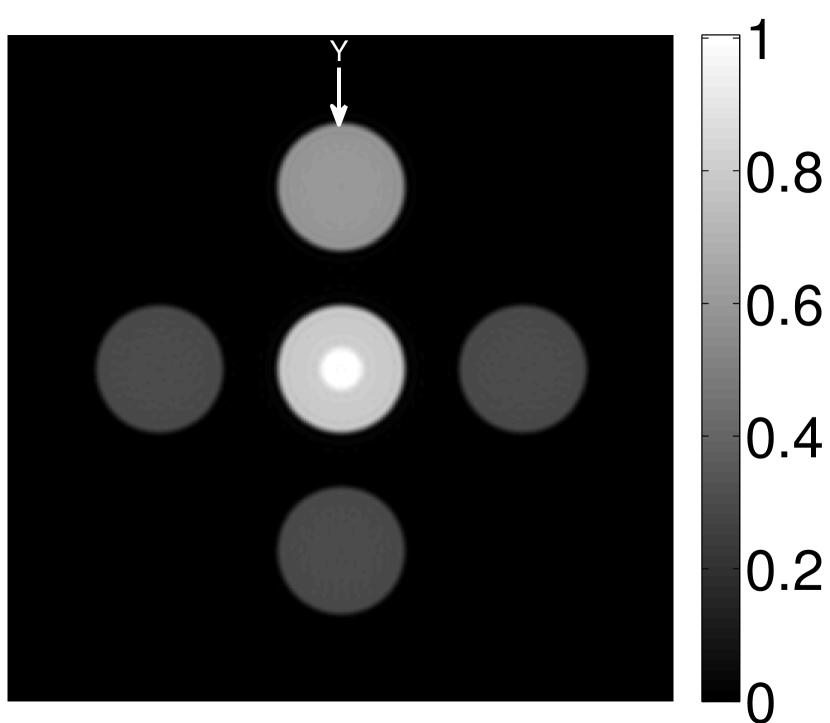

The numerical phantom shown in Figure 1(a) was employed. The phantom had a support area of mm2 and contained six uniform disks that were assigned different values of absorbed optical energy density.

A 2D circular measurement geometry was employed. transducers were evenly distributed on a ring of radius mm that enclosed the phantom. The SOS was assumed to be constant and set at mm/s. Since the simulated data were formed by use of the C-D imaging model in Eqn. (2), no inverse crime was committed. The components of this vector corresponded to equally spaced temporal samples over the interval s. Subsequently, the noiseless voltage vector was obtained by convolving the pressure data with EIR-1 in Figure 1(b).

The reconstruction region ( mm2) was represented by pixels with pixel size mm in each dimension. The initial guess of the EIR employed in the VP algorithm was different than the EIR that was assumed when generating the simulated data. This served to simulate a situation in which an experimentally measured EIR contained errors.

Each element in a real-world transducer array possesses its own EIR. In practice, the differences between the EIRs are sometimes neglected and an EIR corresponding to a single element may be used to represent all elements in the array. In some of the studies below, the EIR employed to initialize the VP algorithm (EIR-2 in Figure 1(b)) and the EIR employed to produce the simulated measurements (EIR-1 in Figure 1(b)) were experimentally measured from two different transducer elements in a circular transducer array (see Sec. VI-B). EIR-1 was measured by temporally integrating the PA signal produced by a point source positioned at the focus of the transducer. EIR-2 was measured by use of the method reported in [RNR2011]. In order to investigate the sensitivity of the VP algorithm to the initialization of the EIR, we employed different EIRs obtained by degrading EIR-1 as described later. When solving the sub-problem in Line-2 of Algorithm 1, was initialized as the zero vector. Algorithm 1 was terminated after 500 iterations, since it was observed that the changes in the reconstructed images with more iterations were negligible. When implemented by use of a single core of an Intel Xeon E5-2640 CPU, each iteration required approximately 7s to complete.

V-B Images reconstructed from noisy data

Figure 7(a) reveals that use of the inaccurate EIR in the conventional iterative method created strong artifacts and distortions. Figures 7(b) confirms that the artifacts and distortions were significantly mitigated when the VP method was employed. Image profiles for both cases are shown in Figures 7(c). The overall accuracy of the recovered EIR, shown in Figure 7(d) and 7(e), was improved, but it contained spurious oscillations.